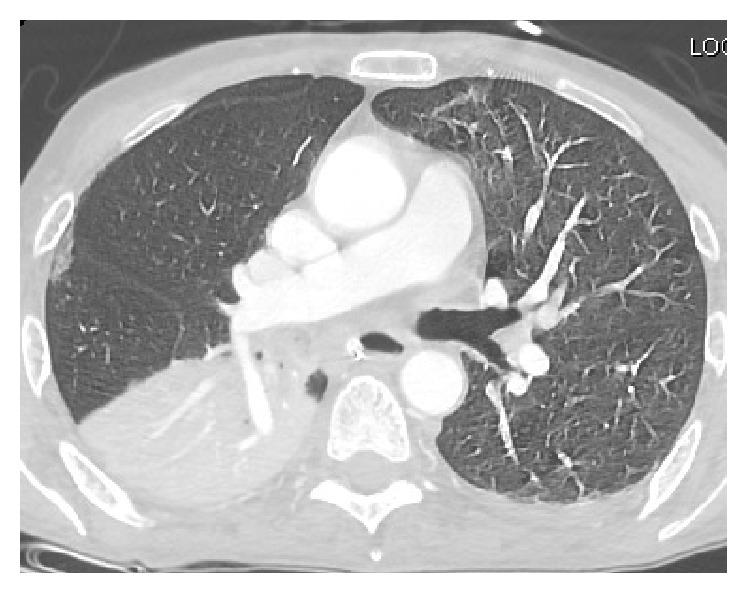

Central pontine myelinolysis (CPM), a potentially fatal and debilitating neurological condition, was first described in 1959 in a study on alcoholic and malnourished patients. It is a condition most frequently related to rapid correction of hyponatremia. Chronic alcoholism associated CPM tends to be benign with a favorable prognosis compared to CPM secondary to rapid correction of hyponatremia. We describe a normonatremic, alcoholic patient who presented with CPM after a rapid rise in his sodium levels. Our case illustrates the fact that CPM can manifest even in patients who are normonatremic at baseline. Rapid rises in sodium levels should be promptly reversed before clinical symptoms manifest in patient with risk factors for CPM irrespective of their baseline sodium levels. Furthermore, clinical evolution of CPM can be difficult to discern from the natural course of alcohol withdrawal delirium, requiring astuteness and maintenance of a high degree of clinical suspicion on the part of the physician.

桥脑中央髓鞘溶解症(CPM)是一种潜在致命且使人衰弱的神经系统疾病,于1959年在一项针对酗酒和营养不良患者的研究中首次被描述。它是一种最常与低钠血症快速纠正相关的疾病。与因低钠血症快速纠正继发的CPM相比,慢性酒精中毒相关的CPM往往预后良好,较为良性。我们描述了一名血钠正常的酗酒患者,其血钠水平快速上升后出现了CPM。我们的病例说明了即使是基线血钠正常的患者也可能出现CPM这一事实。对于有CPM危险因素的患者,无论其基线血钠水平如何,在临床症状出现之前,应迅速逆转血钠水平的快速上升。此外,CPM的临床进展可能难以与酒精戒断谵妄的自然病程相区分,这需要医生保持敏锐并高度临床怀疑。